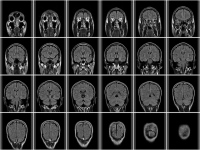

日本では死亡数の第二位を占める心臓疾患の中で、急性心筋梗塞は心不全と並び最も多い死亡原因であるとされている。